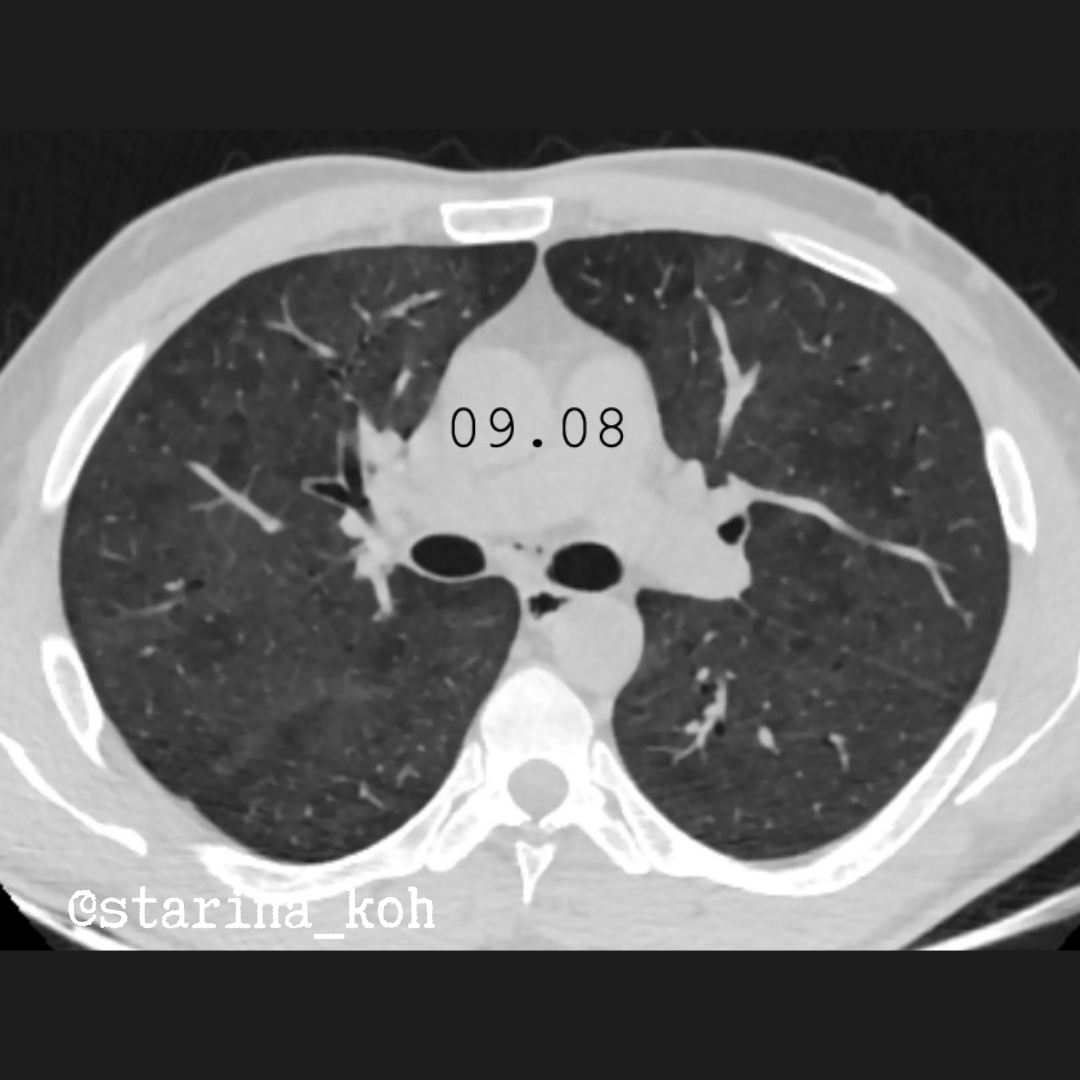

В легких по данным КТ ОГК - участки уплотнения по типу "матового стекла" невысокой интенсивности (от 09.08).

Проводилась терапия метилпреднизолоном, антибактериальная терапия, респираторная поддержка с улучшением, переведен в линейное отделение. Во время нахождения в ОРИТ обнаружены АТ к ВГС (впервые выявлены), анализ на ВИЧ-инфекцию отрицательный. Через неделю в инфекционном отделении у пациента вновь обнаружилось ухудшение - появились эпизоды десатурации до 82% на низком потоке кислорода, которые потребовали применения ВПОТ (25 л/мин). Вне донации кислорода Sat02 падала до 62% (FIO2 45%). Усилилась одышка, ЧДД 28/мин, что в совокупности с низкими параметрами оксигенации крови потребовала перевод на ИВЛ, после чего была выполнена контрольная КТ ОГК - объем поражения нарос, уплотнения "матового стекла" стали более интенсивные, появились зоны "дикой исчерченности". Изменения занимают фактически весь объём легких, а наличие газа в средостении - характерное следствие ИВЛ в режиме PEEP, которая и проводилась пациенту.

По сути, мы видим по данным КТ картину прогрессирующего острого повреждения лёгких - картина неспецифичная и может наблюдать как при вирусных инфекциях, так и при других повреждающих факторах - сепсисе, токсических повреждениях, больших травмах и т.д. Клинически у пациента картина респираторного дистресс-синдрома.